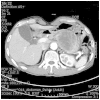

Pure squamous cell carcinoma (SCC) of the stomach is rare and resembles SCC arising elsewhere in the body. The pathogenesis of SCC remains unclear and controversial. At present, <100 cases of primary SCC of the stomach have been reported. The current study presents a case of SCC of the stomach in a 61-year-old male. Total gastrectomy was performed and a 7.0×6.7×4.5-cm tumor with a superiorly located ulcer was identified in the cardia. Upon histological examination, a moderately-differentiated SCC was observed. Tumor cells extended to the serosa, and the perigastric regional lymph node was also involved. No evidence of human papillomavirus (HPV) or Epstein-Barr virus (EBV) infection was identified using a DNA microarray and in situ hybridization, respectively. A post-operative computed tomography scan four months after the gastrectomy revealed tumor recurrence and dissemination of the tumor to the jejunum and pancreas. The patient succumbed to the disease six months later despite the administration of low-dose adjuvant 5-fluorouracil/cisplatin chemotherapy.